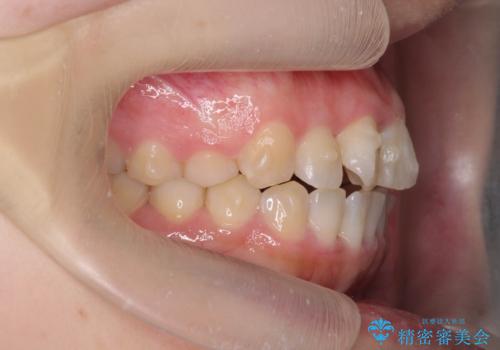

前歯のねじれをマウスピース矯正インビザラインで治療

- 長年気になっている、前歯のねじれの矯正治療を希望され来院されました。

十分にマウスピース矯正インビザラインで治療が可能と判断し、治療を進めることとしました。

長年気になっていた前歯のねじれが、ワイヤーをつけることなく矯正を行うことができ、大変喜んでいただくことができました。